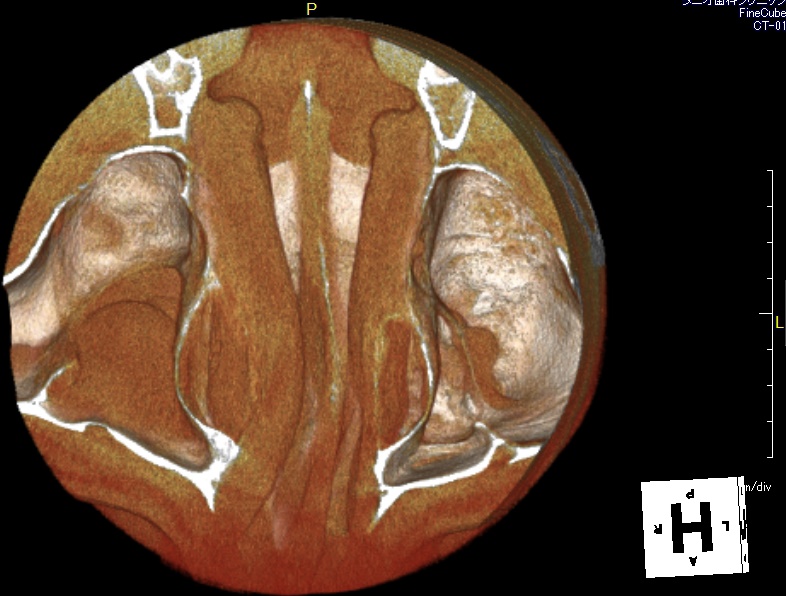

左上6番歯で、添付画像のCTのように、上顎洞内底部で粘膜の肥厚が少し見られます。

上顎洞内のCT画像も添付させてもらいます。

今回対象の左上6番は、上顎洞内のCT画像では向かって右側になります。

向かって左側の大きな肥厚は右上5番歯によるものです。